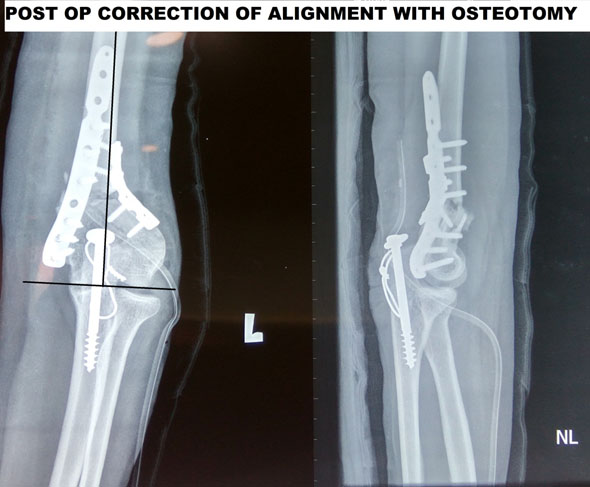

This patient had a previous knee surgery done with an angular deformity in both thigh and the leg bone, which was treated by a combined osteotomy so that an acute angular correction was obtained.

Example of an acute correction by distal femoral and proximal tibial osteotomy

Case Study-

Malunited Supracondylar humerus fracture in a 22 year old yemeni girl presenting for cosmetic appearance and also minimal weakness in the hand due to